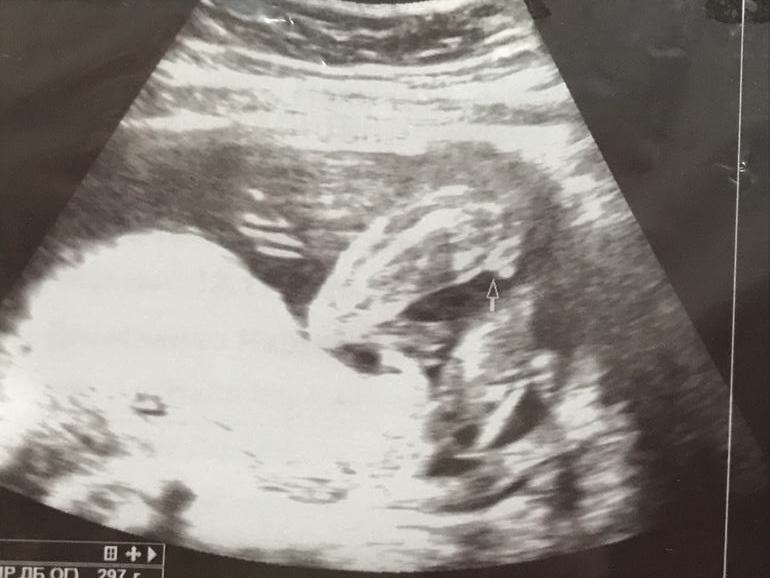

на пирожочек, если смотреть нужно где стрелочка то очень похоже на девочку

Что то довольно большое приданное ,не хочется расстраивать своим предположением( мальчика)

Как тут вообще можно что-то понять)))я кроме головы ничего не поняла, если это конечно голова)))

Ниче не вижу, но первая мысль пришла что девочка🤣при чем не видела что у вас мальчишки

Вроде как на двух узи сказали что девочка. Я после двух пацанов боюсь в это верить, вдруг обломают весь кайф на следующем узи. Но тут вроде все пишут что на девочку похоже, будем надеяться что так и есть)